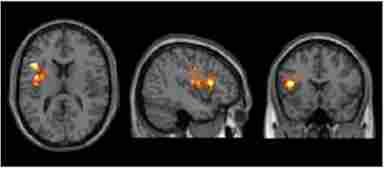

Figure 3 shows the specific brain areas in which the SMART training showed increases in network densities.